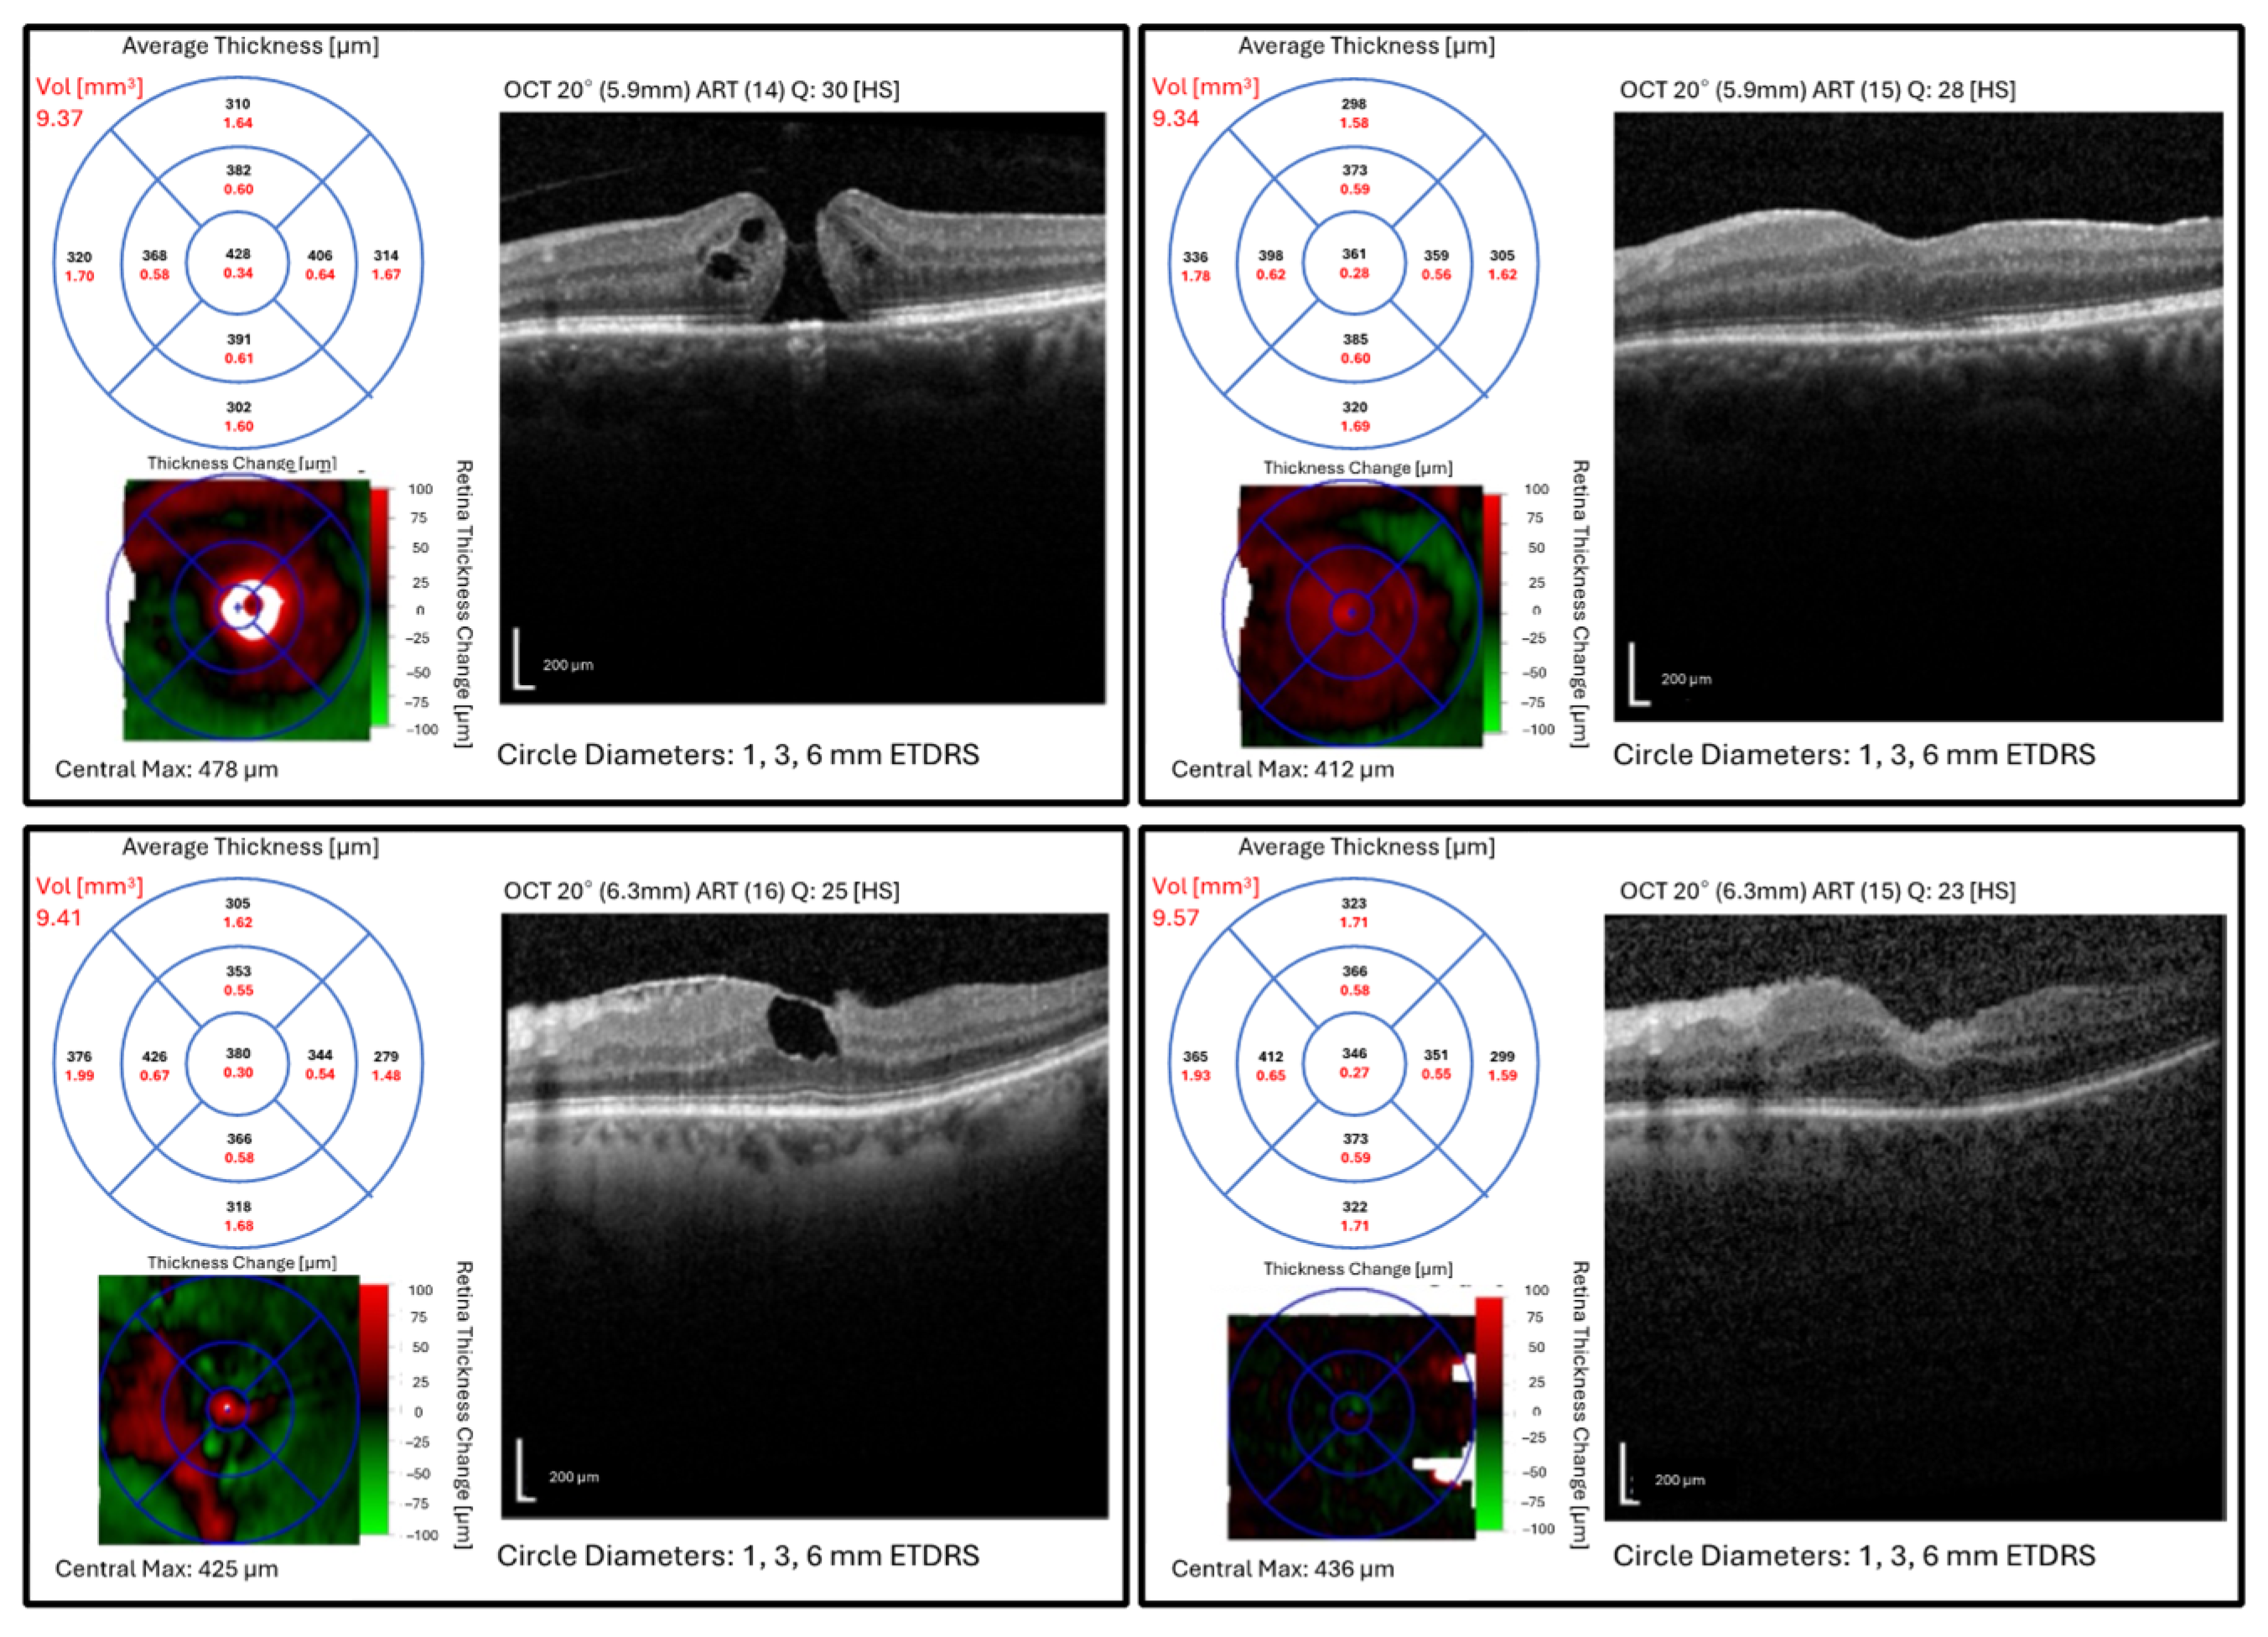

4. Discussion